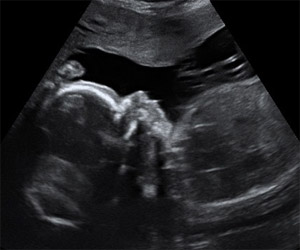

Ecografía de la semana 18: feto de perfil. Cabeza de un bebé de 18 semanas de gestación de perfil (lo vemos a derecha) y tórax (a la izquierda). Se distingue el líquido amniótico -en color negro- en la parte superior del feto. Por encima del mismo se sitúa la placenta.